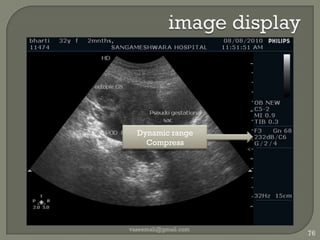

image displayvaseemali@gmail.com76Dynamic range Compress

Dynamic range/compressRatio of largest/smallest echoMeasured in dBFrom tissues 100-150dBDecreases as signals into USGRejection filter : rejects very small & very large echoesTGC60 dB at ADC level vaseemali@gmail.com77

Compress 60dB of interestDisplay : only 20dB brightness levelsNon linear amplifierMore gain for smaller signalsLiver texture: wide Obstetric: less Dark : amniotic fluidBright : bones vaseemali@gmail.com78